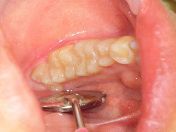

セラミックインレー(e.max)

保険適応の診療では金銀パラジウム合金の詰め物を選択する場合が多々あります。

しかし、審美性はなく金属イオンの流出を考えると生体に優しいとはいえません。

e.maxインレーの登場で、メタルフリー(金属を使用せず)審美性も強度も兼ね揃えたセラミック修復が可能になりました。

何も詰め物がない様に見えるかもしれませんが、白い詰め物で修復されています。